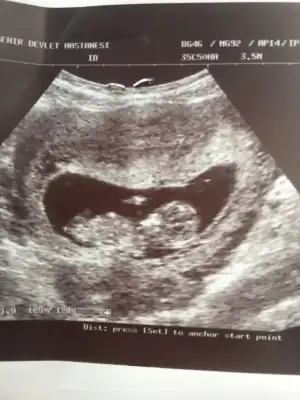

Cok goremedim aslinda ama ilk resimdeki cikintidan erkege benzettm kesin olmamakla birlikte. ne zaman doktor randevunuzKizlar 13+2 deki resim bu tahmin varmi

Sanki kiza benzettim benMerhaba, bugün randevumuz vardı ..goruntumuz aşağıda..10+1 haftalığız.. Belli oluyormu sizce, nedir cinsiyetimiz

Canim 12 haziranda randevumuz.. meraktan catliyorumCok goremedim aslinda ama ilk resimdeki cikintidan erkege benzettm kesin olmamakla birlikte. ne zaman doktor randevunuz